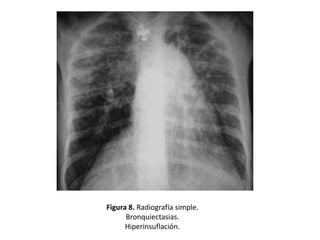

• Hiperinsuflación debida al atrapamiento aéreo

en pacientes con obstrucción funcional (Figura

8)

Figura 8. Radiografía simple.

Bronquiectasias.

Hiperinsuflación.